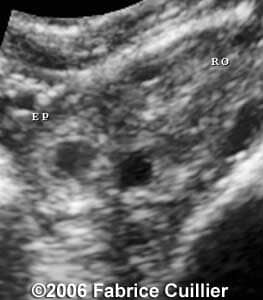

These are some cases of ectopic pregnancy (GEU) using the 2D and 3D scans.

Case 4